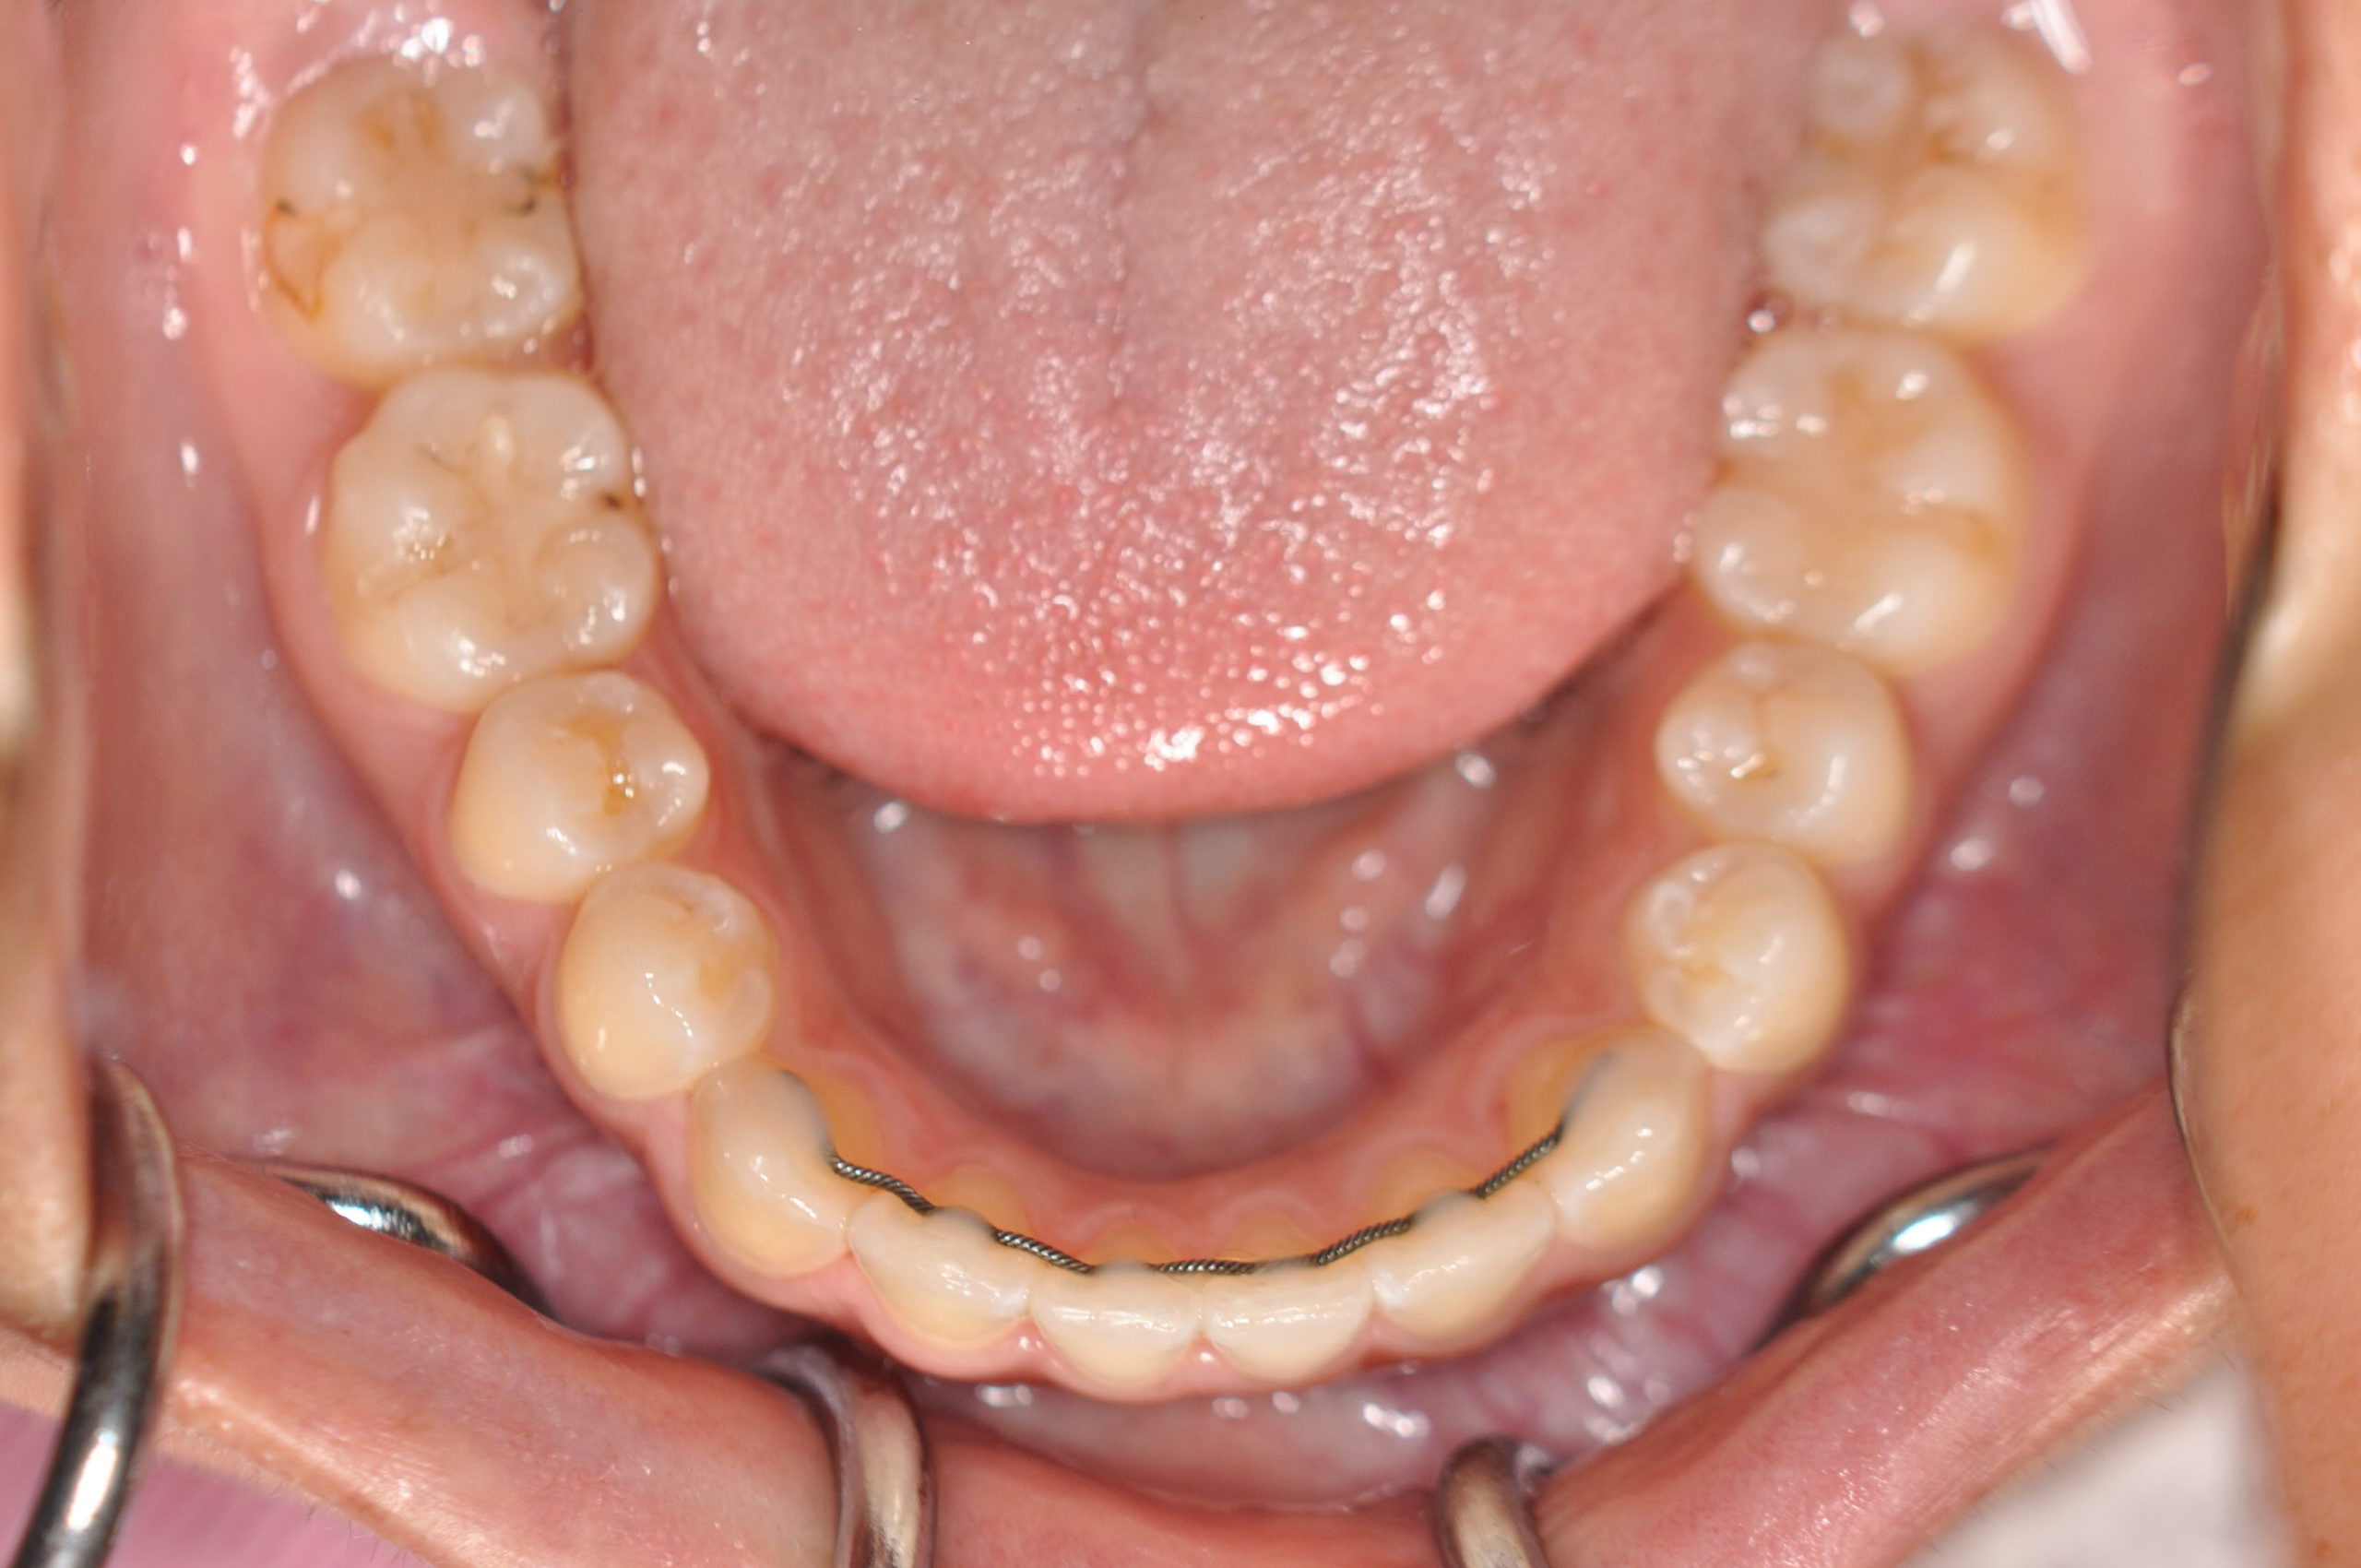

| 治療内容の詳細 | 初診時14歳の女性で、歯のがたつき、かみ合わせを気にされ来院されました。 検査の結果、上下顎前歯部叢生および開咬を伴うアングルⅠ級不正咬合と診断しました。 治療としては、非抜歯の上、セルフライゲーションブラケット装置(デーモンシステム)と マウスピース矯正装置(インビザライン)で配列を行いました。 開咬については、顎間ゴムの協力もあり改善されました。 治療期間は、2年2ヶ月でした。 |